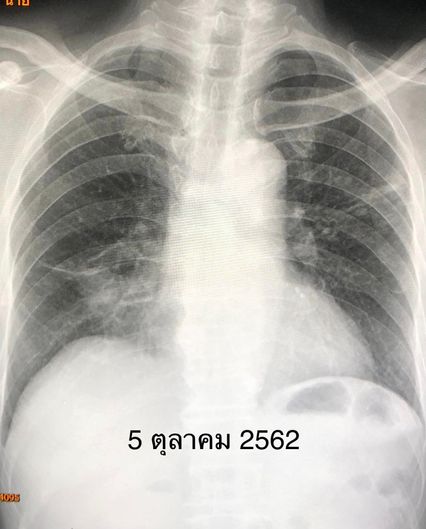

“ผลตรวจร่างกาย ฟังเสียงปอดพบความผิดปกติ เมื่อเอกซเรย์ปอดมีฝ้าขาวทั้งสองข้าง แพทย์จึงสั่งเก็บเสมหะส่งย้อมเชื้อพบวัณโรค 1+ ตรวจรหัสพันธุกรรมพบเชื้อวัณโรคไม่ดื้อยาริแฟมพิซิน เพาะเชื้อขึ้นวัณโรคไวต่อยาไอโซไนอะซิด ริแฟมพิซิน และอีแธมบูทอล สรุปว่า ผู้ป่วยเป็นวัณโรคปอดชนิดไม่ดื้อยา ได้เริ่มยาไอโซไนอะซิด ริแฟมพิซิน พัยราซินาไมด์ และอีแธมบูทอล หลังกินยาวัณโรค 2 สัปดาห์ ผู้ป่วยคลื่นไส้ อาเจียน เบื่ออาหาร ค่าเอนไชม์ตับขึ้นสูง SGOT 312, SGPT 199 แพทย์สงสัยว่าแพ้ยาริแฟมพิซินทำให้ตับอักเสบ จึงหยุดยาริแฟมพิซิน ให้ยามอกซิฟลอกซาซิน (Moxifloxacin) แทนยาริแฟมพิซิน ค่าเอนไชม์ตับลดลง SGOT 57, SGPT 36” หมอมนูญระบุ

เคสนี้แพทย์รักษาด้วยการให้กินยาวัณโรคไอโซไนอะซิด พัยราซินาไมด์ อีแธมบูทอล และมอกซิฟลอกซาซิน ต่อเนื่อง 1 ปี ไม่ไอ มีความอยากอาหาร น้ำหนักขึ้น 14 กิโลกรัม ผลเอกซเรย์ปอดดีขึ้นมาก หลังหยุดกินยา 4 ปี วัณโรคไม่กลับมาใหม่ เอกซเรย์ปอดยังมีร่องรอยวัณโรคเก่าบ้าง